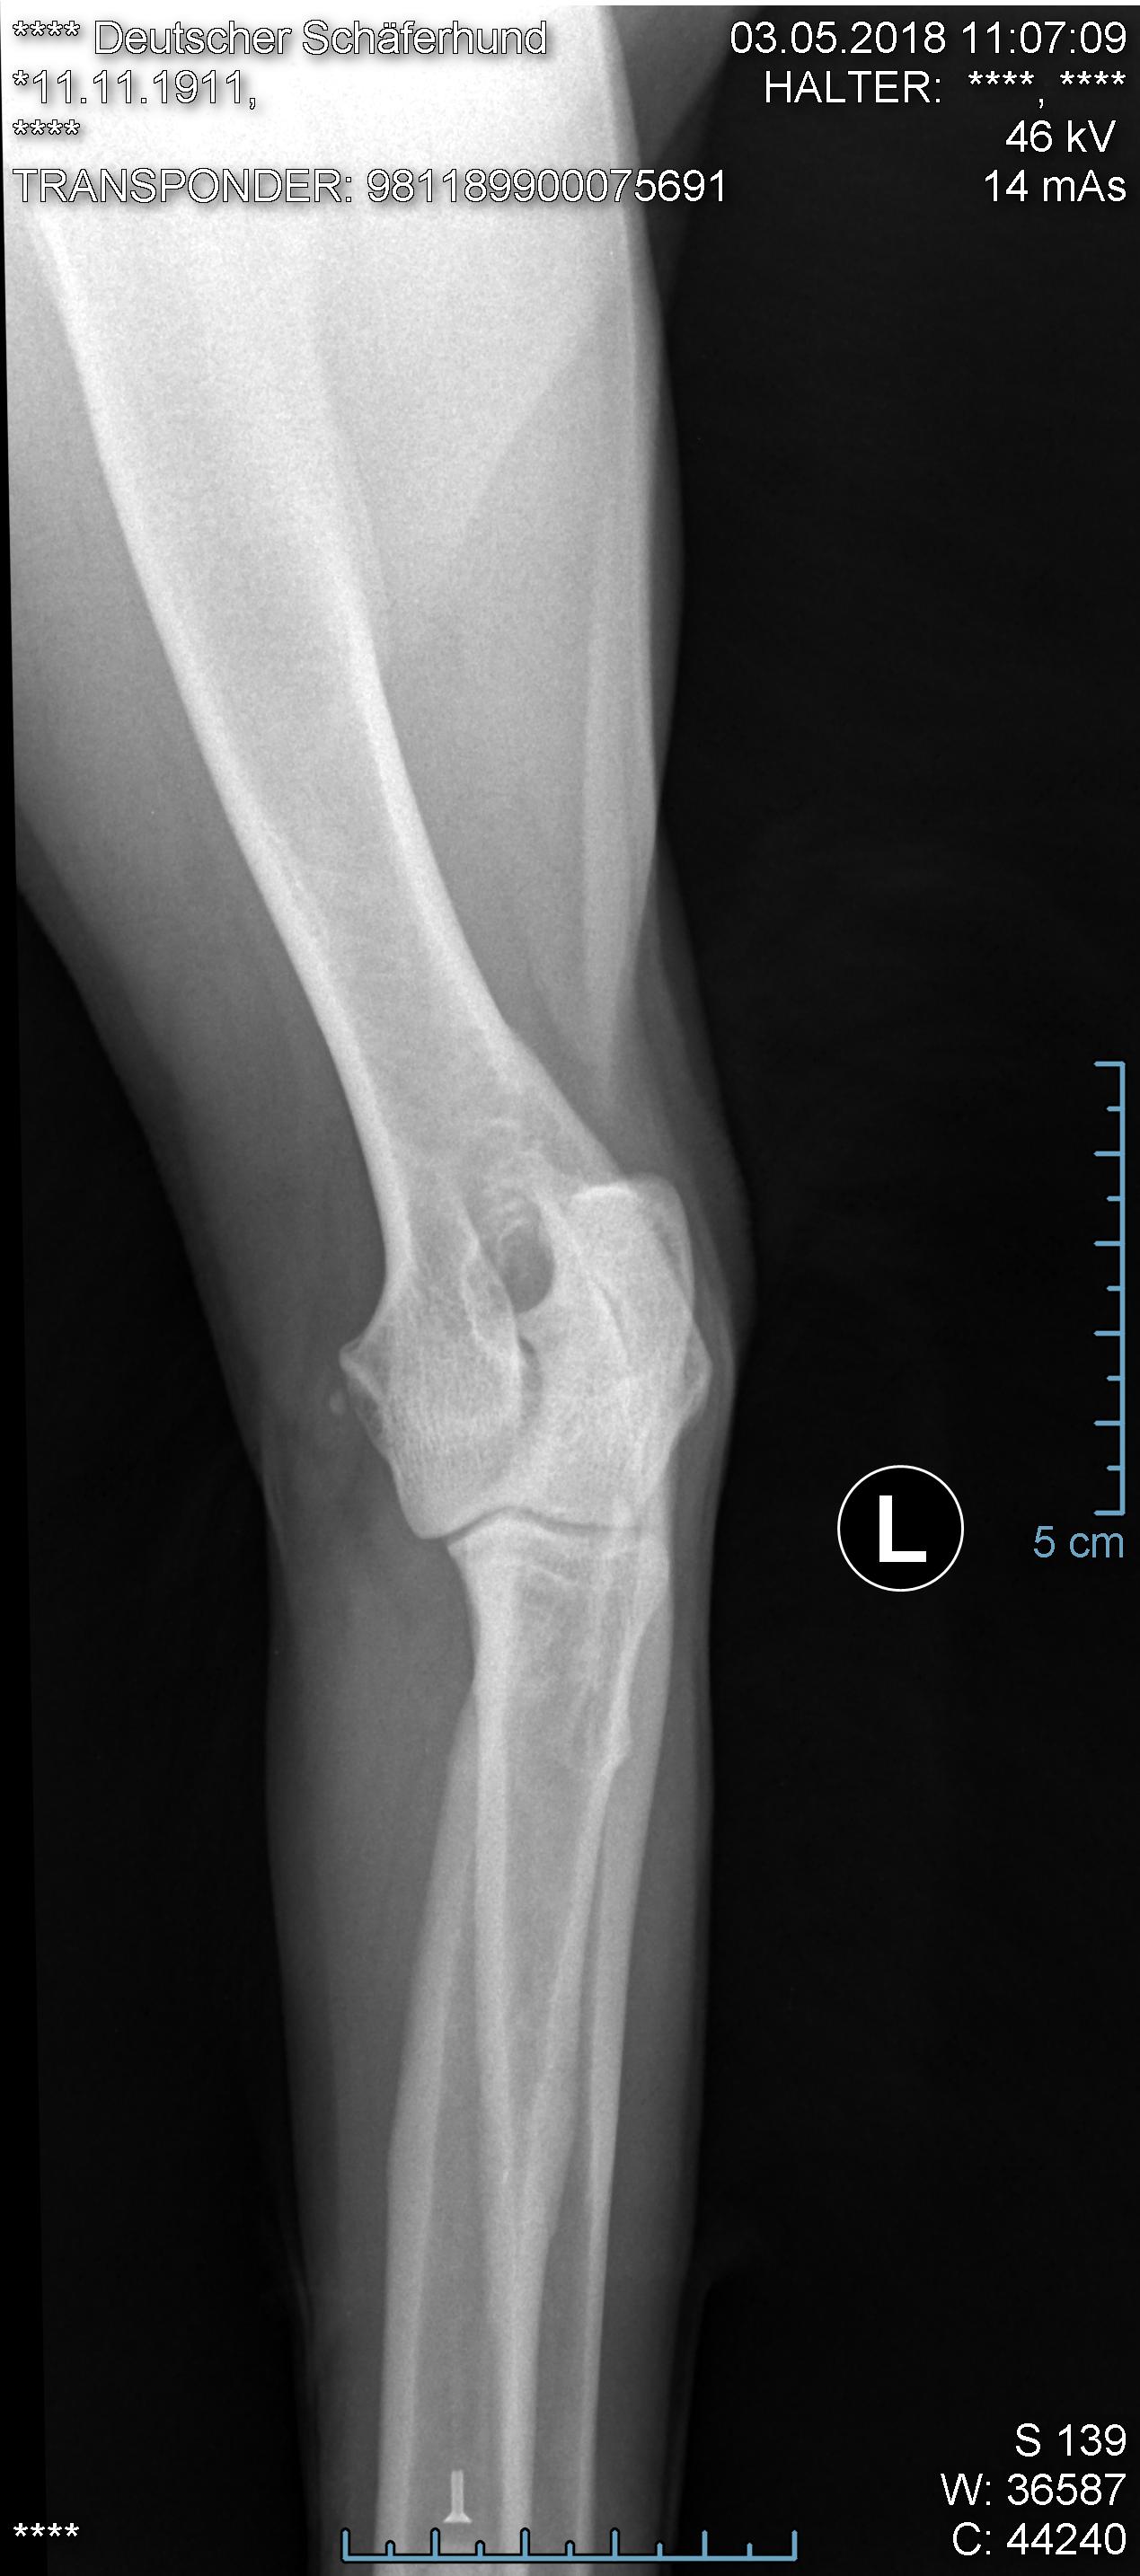

Hier ist eine HD-ED Aufnahme von unserer Isis von KaTum,  alles Top